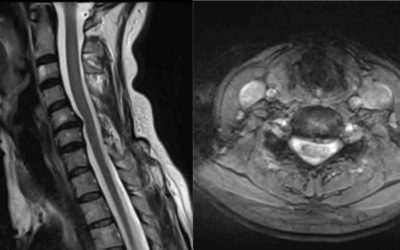

Mielopatía cervical: causas, síntomas y tratamiento

La mielopatía cervical es un trastorno que afecta la médula espinal en el cuello, común en personas mayores pero no exclusivo de ellas. Resulta de la compresión medular y provoca síntomas neurológicos variados. Entre las causas, se encuentran degeneraciones por edad, hernias de disco y traumatismos, todos afectando significativamente la calidad de vida. Un diagnóstico y tratamiento oportunos son fundamentales para mejorar el pronóstico y el bienestar del paciente.